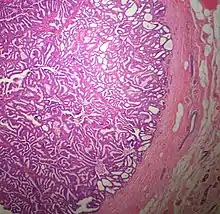

The microscopic histopathology of typical PDCIS lesions (refer to adjacent high-power photomicrograph) prepared with a hematoxylin and eosin stain consists of mammary ducts that have papillary fronds (i.e. thin, finger-like or leaf-like structures) lined with one or several layers of neoplastic, columnar-shaped epithelial cells (i.e. tall, narrow cells with their nuclei close to the site of their ductal attachment).[4] The fronds have branching fibrovascular cores. Epithelial cells lining the fronds' inner surfaces commonly form solid, cribriform (i.e. large nests of cells perforated by many rounded, variably sized spaces), or micro-papillary patterns. There may be a second population of epithelial cells lining the papillae that have abundant clear cytoplasm in addition to the usual neoplastic epithelial cells which line the papillae. These cells, which are not myoepithelial cells, have been termed globoid cells.[7] They have eosinophilic cytoplasm (i.e. pink or red cytoplasm due to its uptake of eosin stain).[6] PDCIS tumors with these cells have been termed dimorphic variants of PDCIS.[3] Myoepithelial cells are typically present at the periphery of the fronds but absent within the involved ducts.[4][7] The presence of a fibrous capsule and/or absence of peripherally located myoepithelial cells are strong indicators that the tumor is an ESP rather than a PDCIS.[3] PDCIS tissues may also contain areas of "Comedo-type necrosis", i.e. areas where dead cells have accumulated.[6]

The microscopic histopathology (refer to adjacent high-power photomicrograph) of EPC tissues typically shows papillary structures with fibrovascular cores and proliferating neoplastic epithelial cells growing within cystic spaces, all of which are enclosed within a dense fibrous capsule. In general, EPC tumors do not have areas of neuroendocrine degeneration or myoepithelial cells.[6] The presence of a dense fibrous capsule distinguishes EPC from other papillary breast tumors, particularly PDCIS;[3] the absence of neuroendocrine differentiation areas helps distinguishes EPC from SPC tumors;[3] and the absence of peripherally located myoepithelial cells helps distinguish EPC from PDCIS tumors.[7] EPC tumors may be totally contained within their fibrous capsules or have one or more areas that have invaded through the capsule to normal breast tissues and/or chest muscles; these two variants are termed in situ EPC and infiltrative EPC, respectively.[3][5] In a study of 25 individuals with EPC, 14 had in situ and 11 had invasive disease with 6 of the invasive tumors rated as high grade (see high grade tumors) based on their microscopic histopathology.[5] Rarely, EPC tumors metastasize to nearby sentinel lymph nodes, other nearby axillary lymph nodes, and/or distant tissues; these metastases have in general shown papillary morphologic features similar to their primary tumors.[6] Uncommonly, EPC tumors co-exists with nearby PDCIS,[7] invasive carcinoma of no special type, invasive cribriform carcinoma of the breast, mucinous carcinoma, or tubular carcinoma[3] tumors.

Microscopic histopathological analyses of SPC lesions (refer to adjacent high-power photomicrograph) generally show tumors with multiple circumscribed nodules of expanded ducts filled with neoplastic epithelial cells which may appear spindle-shaped or plasma cell-like, have red to pink cytoplasm due to the uptake of eosin after staining with hematoxilin & eosin, and eccentrically-placed nuclei. Rarely, signet ring-shaped cells are present. The tumors may have cystic and hemorrhagic areas. Myoepithelial cells are found within and at the periphery of these tumors. The papillary architecture seen in the other SCB types is in general not apparent; rather, pseudo-rosettes (i.e. radial arrangements of neoplastic cells around small blood vessel) and nuclear palisading (i.e. parallel arrangements of the nuclei in rows of tumors that resembles picket fences) around stromal cores (i.e. supporting tissues) may be seen. SPC tumor tissues typically (>50% of cases) have areas of neuroendocrine differentiation. The presence of these areas strongly supports the diagnosis of SPC.[21] The signet ring-shaped cells in these tumors contain cytoplasmic mucin-containing vacuoles which push their cells' nuclei to one side.[10] Mucin may also occur outside of cells in these lesions. The presence of signet ring-shaped cells bearing mucin-containing vacuoles with or without extracellular mucin strongly supports the diagnosis of SPC. SPC is considered invasive when the tumor nests have a characteristic jigsaw growth pattern with ragged and irregular margins with the loss of myoepithelial cells at the site(s) of invasion.[21] Rarely, invasive SPC occurs with nearby invasive carcinoma of NST, lobular carcinoma, cribriform carcinoma, or tubular carcinoma breast tumors.[3]

Since many of the earlier published cases of IPC actually appear to be variants of invasive EPC or SPC, there is little consistent pathological data on IPC.[7] Studies on the microscopic histopathology of IPC have reported finding (refer to the adjacent high-power photomicrograph): 1) blunt papillae or ductal structures consisting of neoplastic epithelial cells surrounding a fibrovascular core;[1] 2) papillae located in dilated ducts and variably sized microcysts plus foci of necrosis (i.e. dead cells);[4] 3) tumors totally dominated by fibrovascular cores covered with neoplastic epithelium cells;[3] and 4) tumors showing >90% papillary morphology invading nearby breast tissue and/or sub-mammary chest muscles.[22] Studies do agree that IPC tumors have, by definition, one or more sites that have invaded nearby breast and/or muscle tissue, lack myoepithelial cells at their invasion sites, and generally lack a peripheral fibrous capsule; these features are important for diagnosing IPC.[6][7][20][22] Rarely, ductal carcinoma in situ lesions are present near IPC.[3] A retrospective histopathological analysis of the tumor tissues in 1,147 individuals with IPC reported that 89.3%, 83.4%, and 2.4% of the cases had tumor cells which respectively expressed the estrogen receptor, progesterone receptor, and HER2/neu protein (however, 46.4% of the cases were not tested for the HER2/neu).[1] In a second histopathological study of 44 individuals diagnosed with IPC, 72.7% had tumor cells that expressed the estrogen receptor, 72.7% had tumor cells that expressed the progesterone receptor, and 13.6% had tumor cells that expressed the HER2/Neu protein.[22] No specific genetic alterations have been as yet been clearly associated with the tumor cells in individuals diagnosed with IPC.[6]